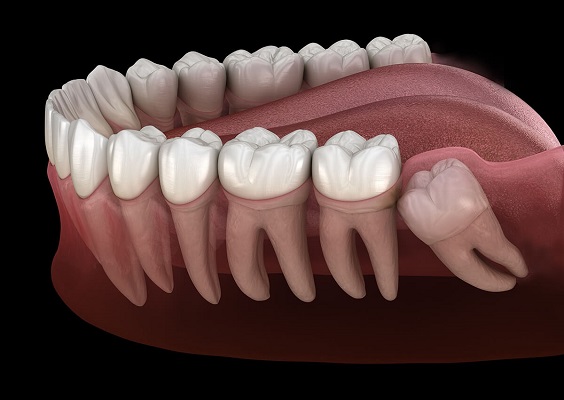

Gömük dişlerin çıkarılması

Gömük köpek dişlerinin cerrahi olarak sürdürülmesi

Diğer dişlere sürme sırasında cerrahi yardım